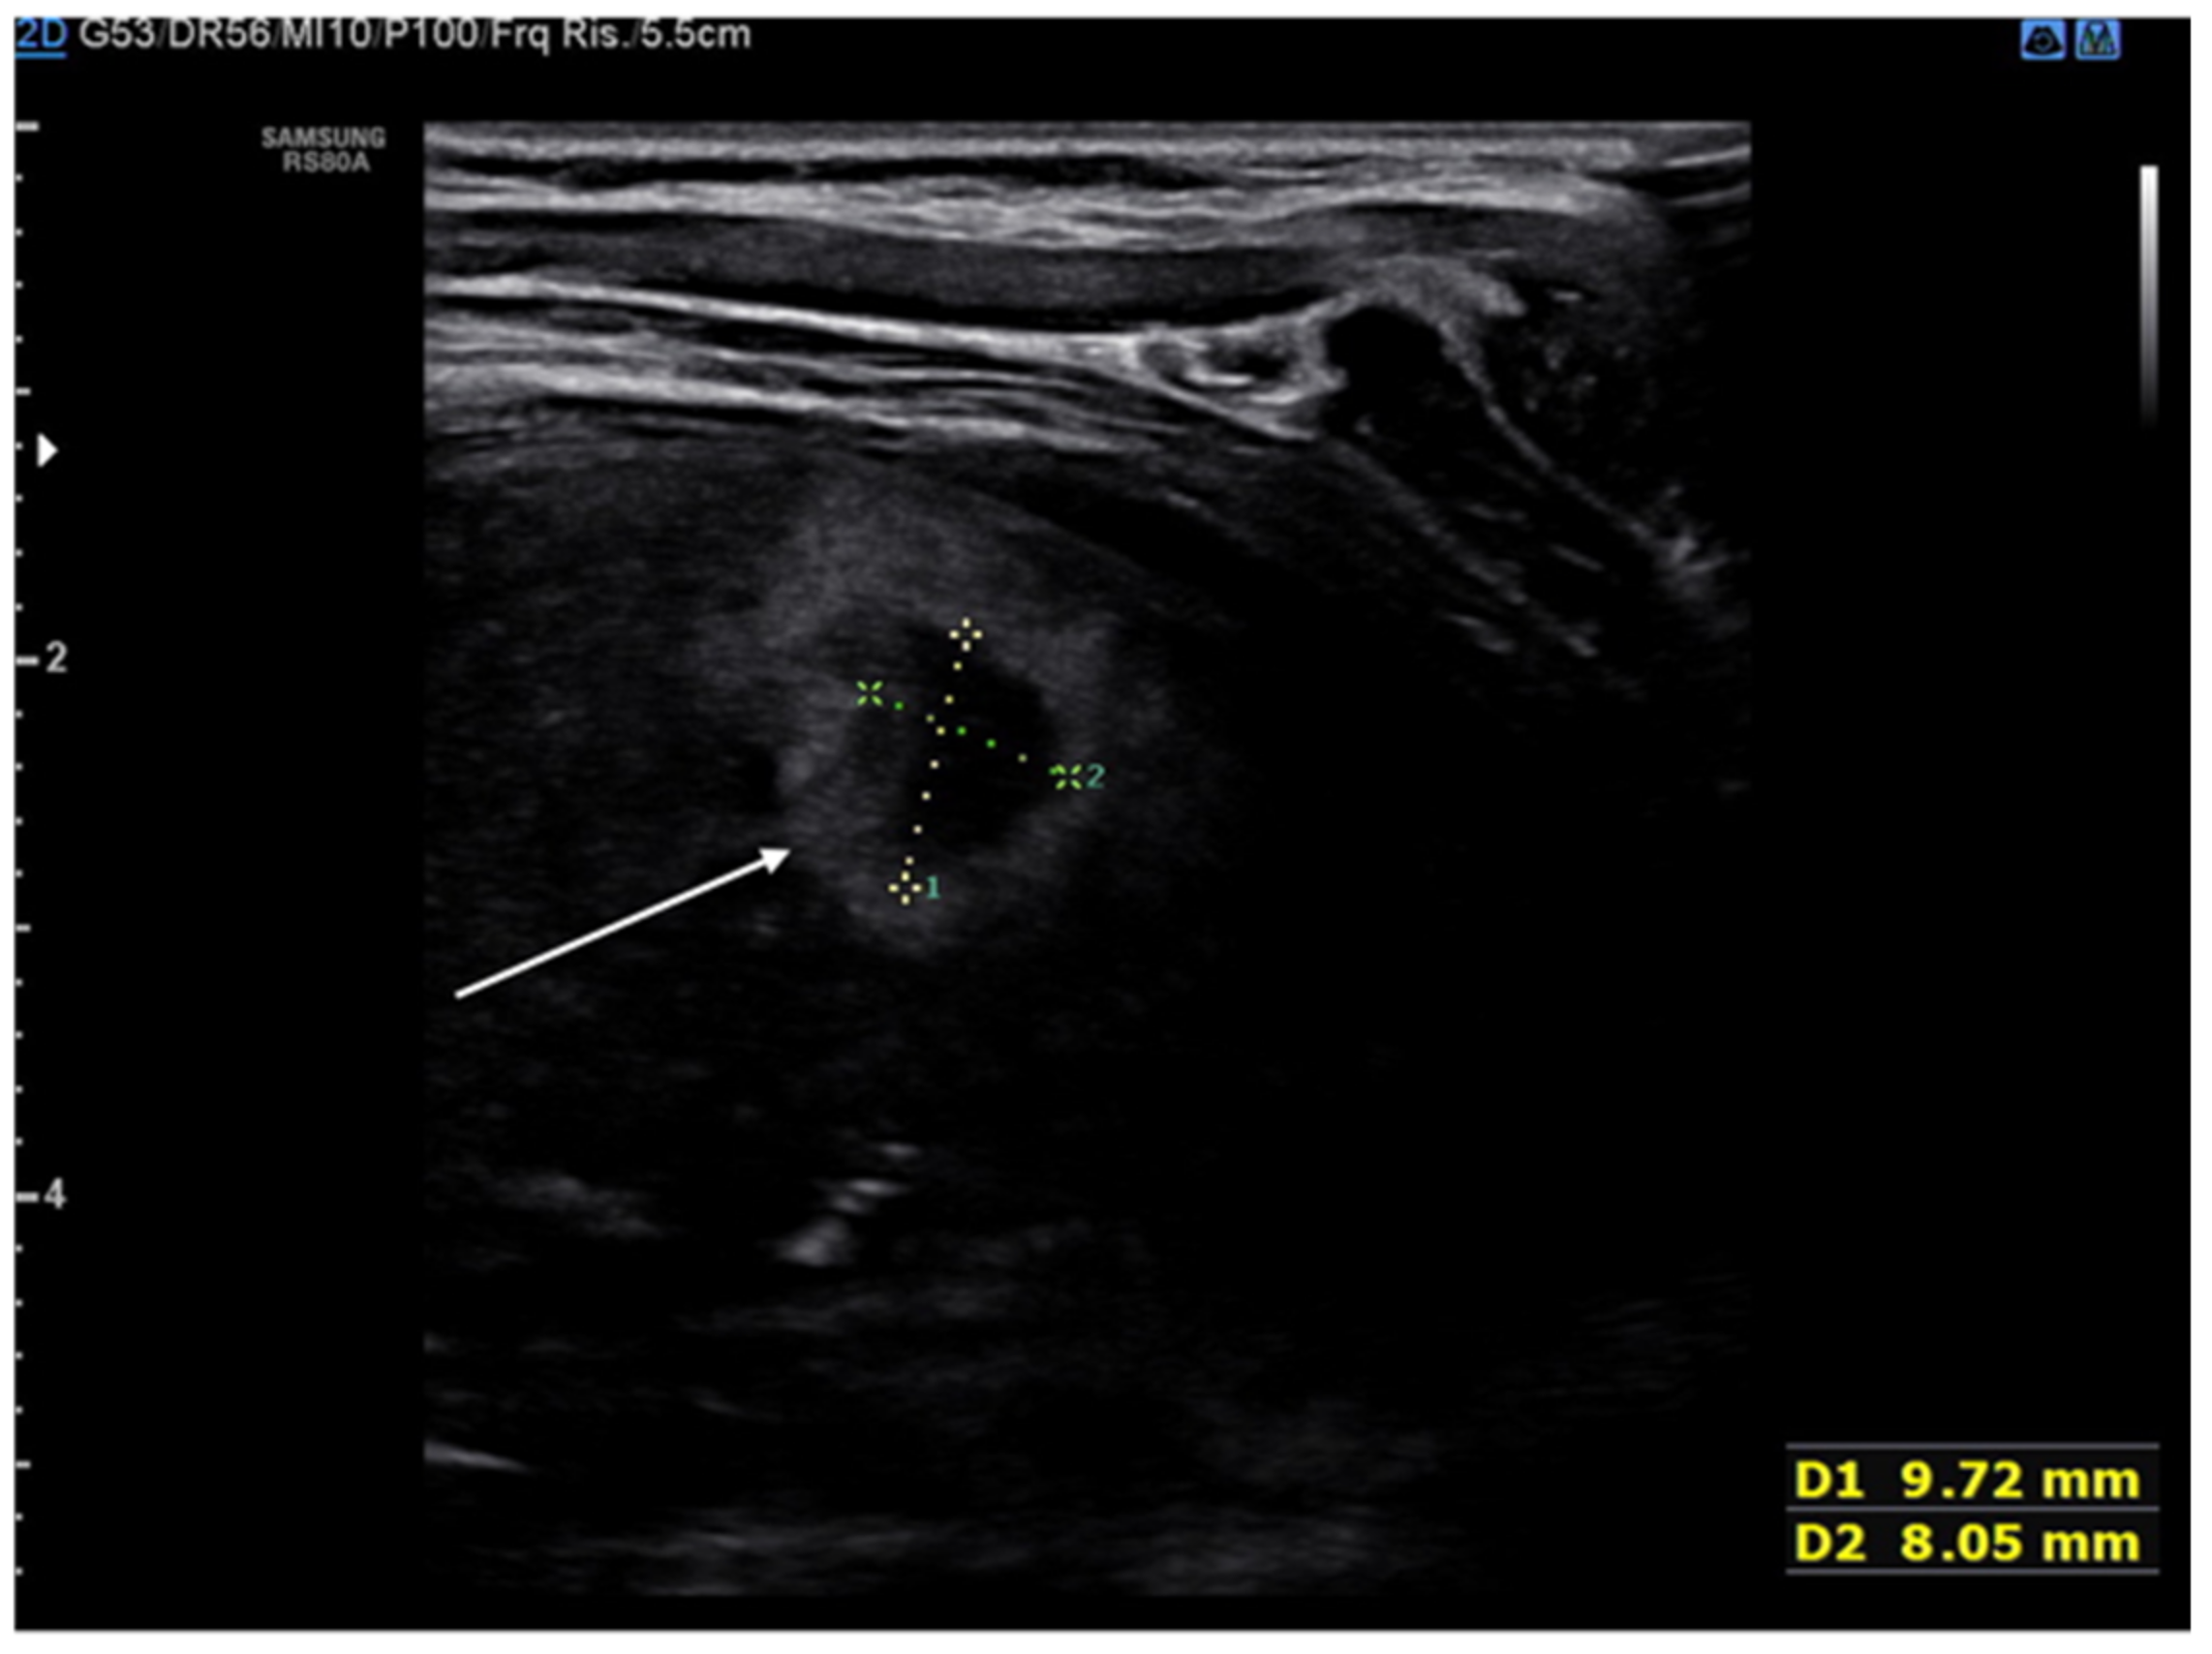

The lung abscess appears as a well-demarcated capsular structure surrounding a hypoechoic core without internal vascularity on color Doppler (Figure 11). Furthermore, it is possible to distinguish lung abscess from pyopneumothorax through the presence of all four specific signs: air-fluid level, synchronous movement of air-fluid levels with breaths, loss of gliding sign above the air-fluid level and the suspended microbubble sign (punctate hyperechoic pinpoints with shadows that move more or less randomly with respiratory movement within the pleural effusion) [56,57].

Figure 11. Hypoechogenic capsule lesion with irregular, hyperechogenic edges suggestive of lung abscess (white arrow).